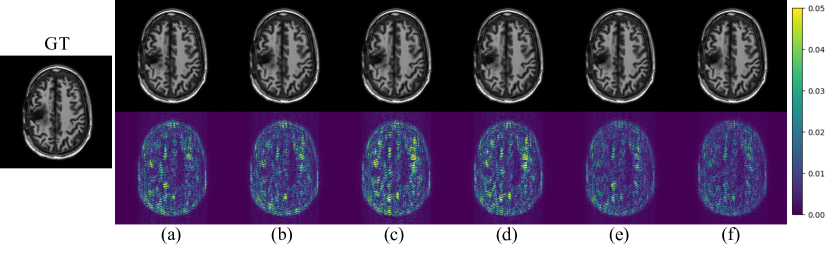

Figure 3: Qualitative results and error maps of ablation study on HPKS with AF=4. (a) UC-CRNN. (b) UC-CRNN + RM. (c) OC-CRNN. (d) OC-CRNN + RM. (e) UC-CRNN + OC-CRNN. (f) UC-CRNN + OC-CRNN + RM (proposed OUCR).

Ablation Study. We conduct a detailed ablation study to separately evaluate the effectiveness of using OC-CRNN, UC-CRNN, and RM in the proposed framework. The results are shown in Table 2. We start with only using OC-CRNN and UC-CRNN. It can be noted that the performance of OC-CRNN is lesser than UC-CRNN, since even though OC-CRNN captures the low-level features properly it does not capture most high-level features like UC-CRNN. Then, we show that adding RM with each individual module can improve the reconstruction quality. Finally, combing both CRNN networks with RM (proposed OUCR) results in the best performance. Fig. 3 illustrates the qualitative improvements after adding each major block, which is consistent with the results reported in Table 2. Moreover, we observe that increasing the number of CRNN iterations can further improve the performance of the proposed OUCR, but consequently leads to lower computational efficiency. Due to space constraint, an ablation study regarding CRNN iterations, k-space analysis on fastMRI dataset, and more visualizations are provided in the supplementary material.